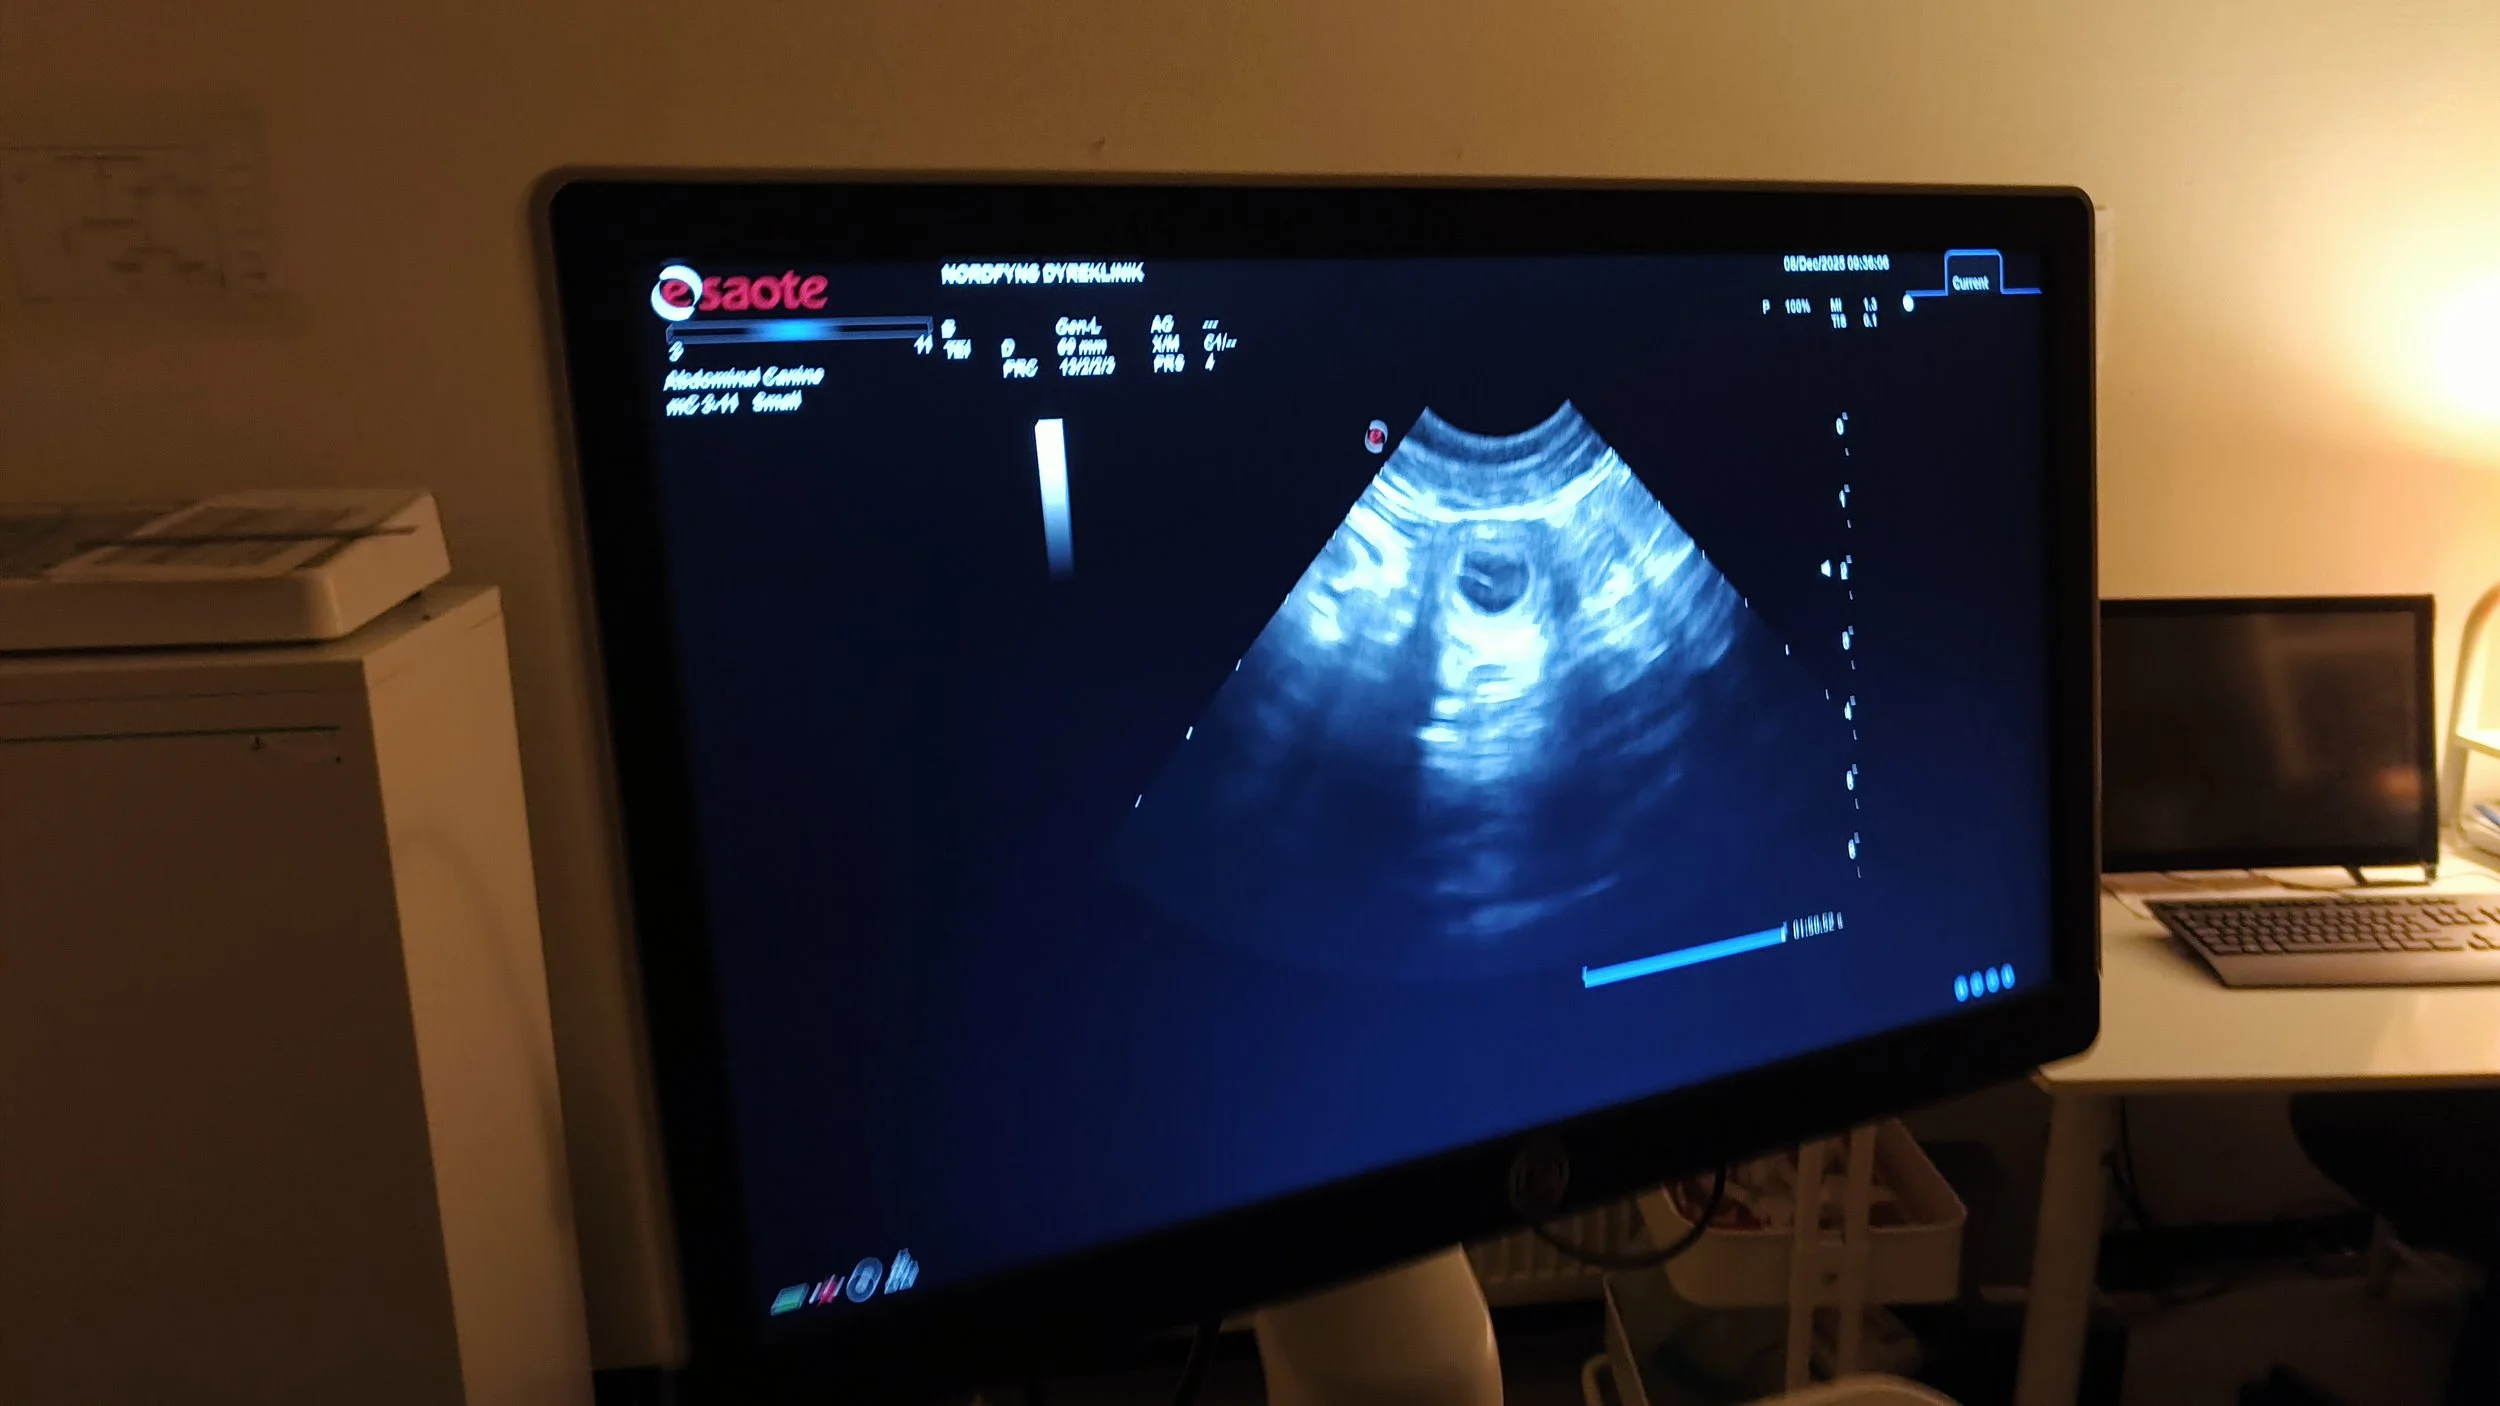

Das Scanning hat schöne, kleine “Blasen” gezeigt - wir freuen uns. Juno freut sich immer noch, macht gerne Spaziergänge, spielt gerne, aber sie wird schneller müde. Und sie frisst mit Appetit!